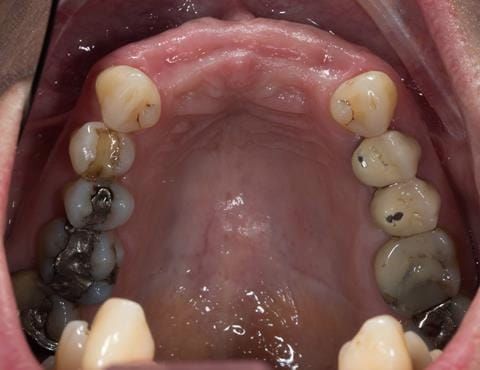

- UR2 peri-radicular periodontitis with a peri-radicular area on the root apex. Retrograde amalgam filling from a previous apicectomy. No visible root canal or root canal filling. Large circumferential marginal gap between the crown and tooth. Large post and core present. Very little tooth structure remaining resulting in a fragile tooth with increased potential for fracture.

- UR1 peri-radicular periodontitis with a small peri-radicular area on the root apex with wide blunderbuss apex. Radio-opaque root canal filling present approximately 3 mm short of the radiographic apex. Large circumferential marginal gap between the crown and tooth. Large post and core present. Very little tooth structure remaining resulting in a fragile tooth with increased potential for fracture.

- UL1 peri-radicular periodontitis with a peri-radicular area on the root apex. Retrograde amalgam filling from a previous apicectomy. Visible root canal space with no sign of root canal filling. Large circumferential marginal gap between the crown and tooth. Large post and core present. Very little tooth structure remaining resulting in a fragile tooth with increased potential for fracture.

- UL2 peri-radicular periodontitis with a peri-radicular area on the root apex. No visible root canal or root canal filling. Large circumferential marginal gap between the crown and tooth. Large post and core present. Very little tooth structure remaining resulting in a fragile tooth with increased potential for fracture.

- Other than the maxillary incisors the remaining dentition was in marginally better condition being moderately to heavily restored. Many will probably require replacement and restoration from time to time mainly from wear and tear owing to occlusal forces.

Following consultation and second discussion appointment the patient chose to have option 3 namely, a maxillary cobalt chromium based partial denture/protective occlusal splint. The clinical situation and treatment process is shown in detail below with photographs. The patient was successfully rehabilitated with this and her quality of life considerably improved. The clinical work was provided by Finlay and the technical work by Rowan.